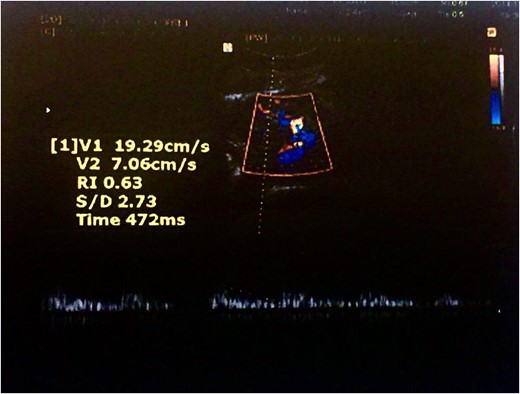

Color Doppler ultrasound of the transplanted kidney 2 months after surgery.

Color Doppler ultrasound of the transplanted kidney 2 months after surgery in the zoomed area of the image.